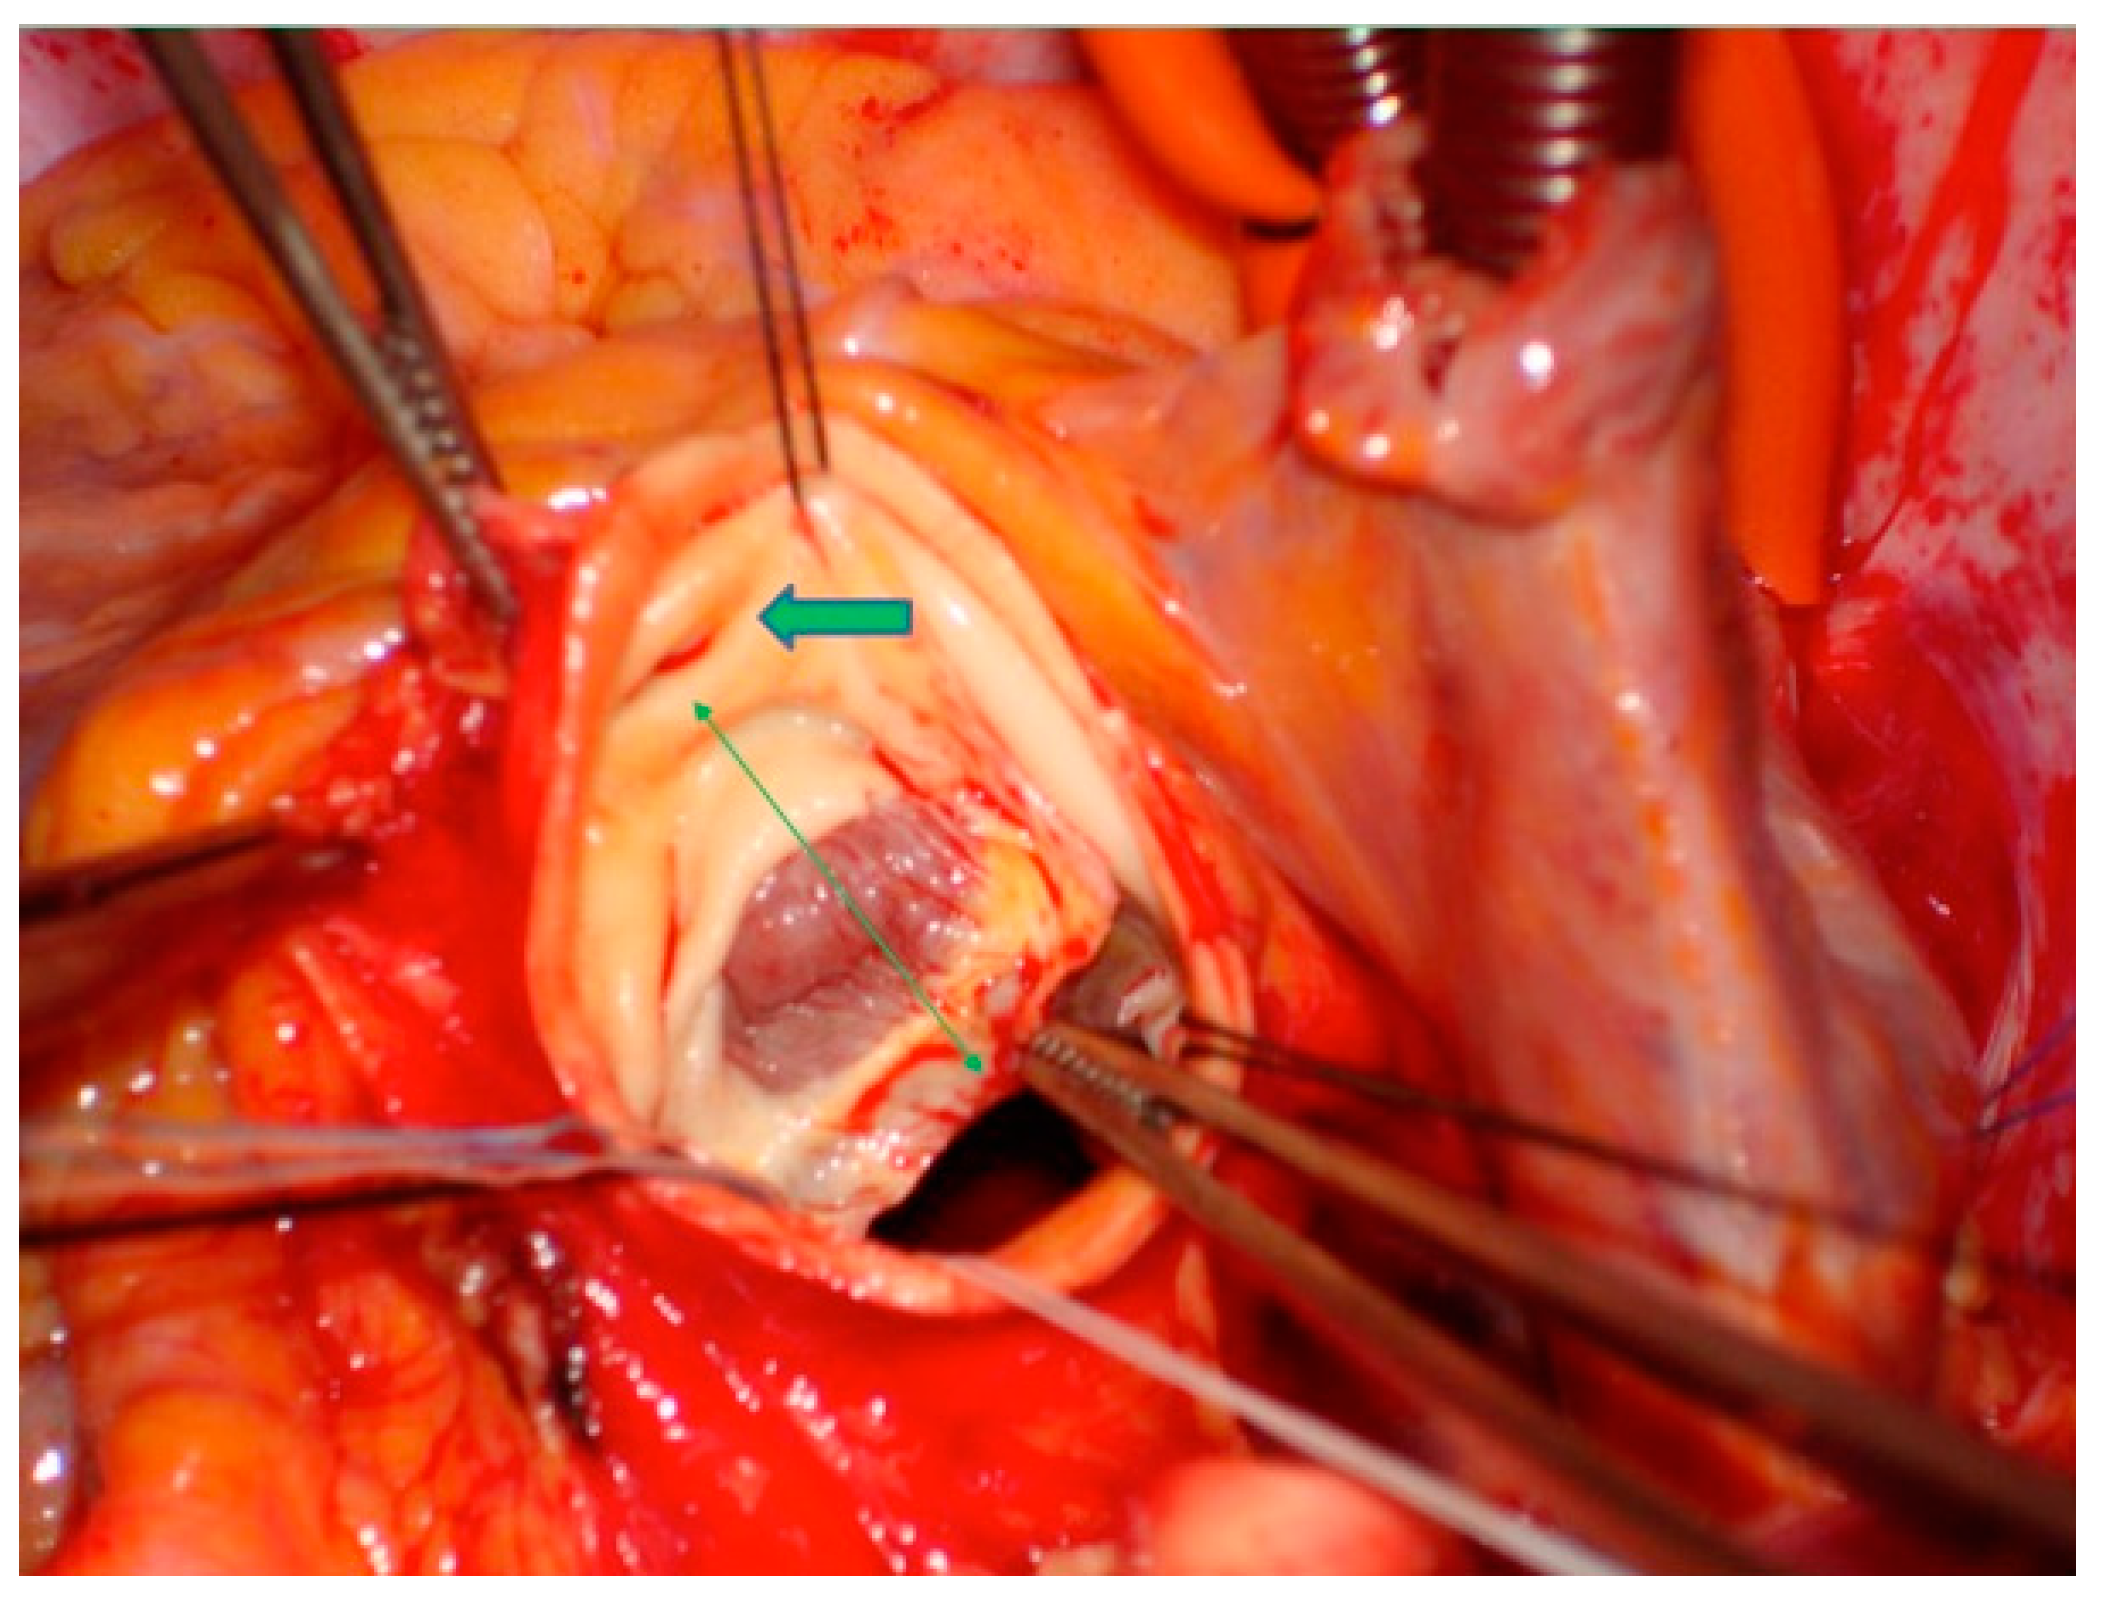

2.4. Surgical Technique